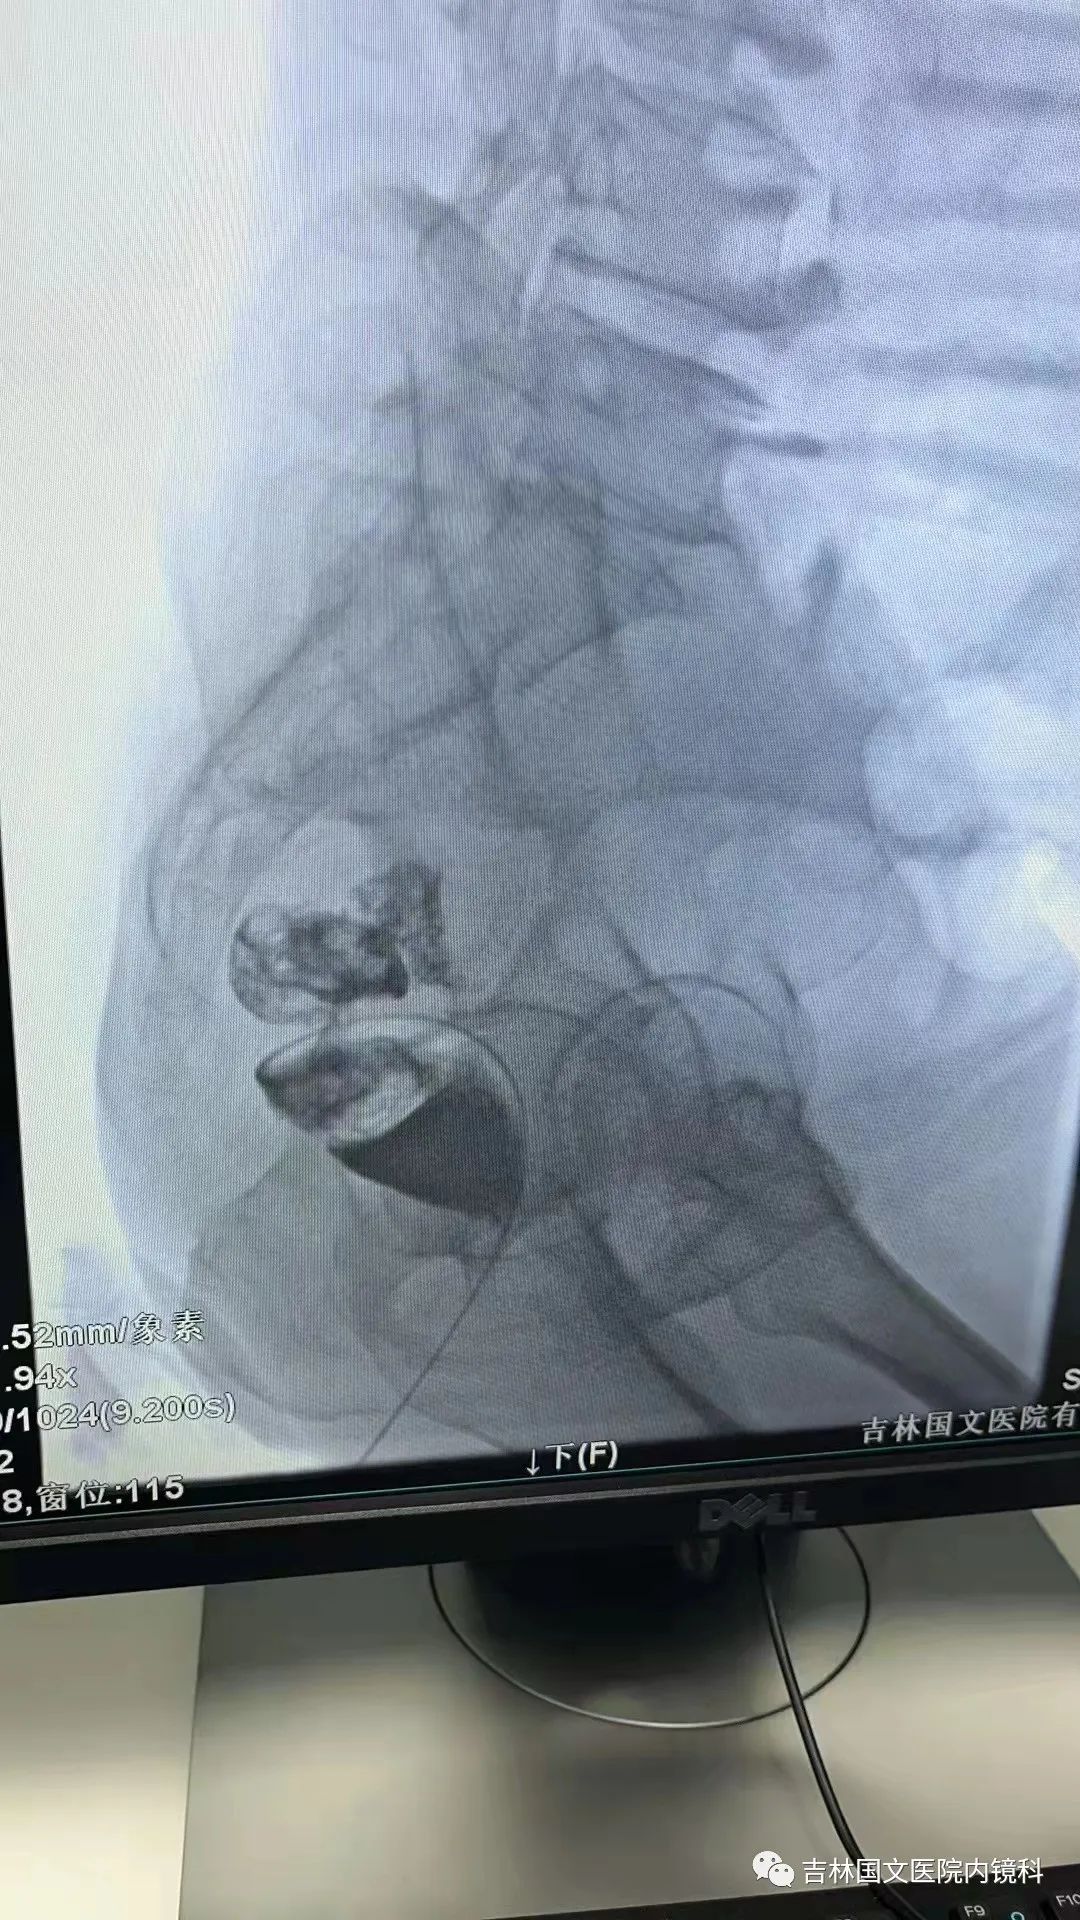

腸道支架置入

這是一位腸癌的患者,腫物生長(zhǎng)在乙狀結(jié)腸,將腸腔堵得只剩一個(gè)小孔,糞便自然很難通過(guò),腸梗阻的癥狀使患者十分難受,已多天未排氣排便,患者十分瘦削,開(kāi)始侯主任未借助任何工具探查一番,結(jié)果就是腸道太迂曲了,實(shí)在無(wú)法順利將導(dǎo)絲置入,通過(guò)邢主任使用腸鏡在前面引路一直到達(dá)病變部位,這時(shí)候侯主任將帶有外套管的導(dǎo)絲從活檢口插入,外套管抵在小孔處,導(dǎo)絲順利進(jìn)入,第一步成功。第二步就是將支架順著導(dǎo)絲送入指定位置,又是一大難關(guān),導(dǎo)絲十分軟,缺乏支撐力,腸道的彎曲十分陡峭,一用力支架抵在腸道低處,患者痛感極強(qiáng),只能另想辦法,嘗試多次后,在兩位主任的豐富經(jīng)驗(yàn)和堅(jiān)持不懈的努力下,支架順利置入,為患者解除了痛苦。